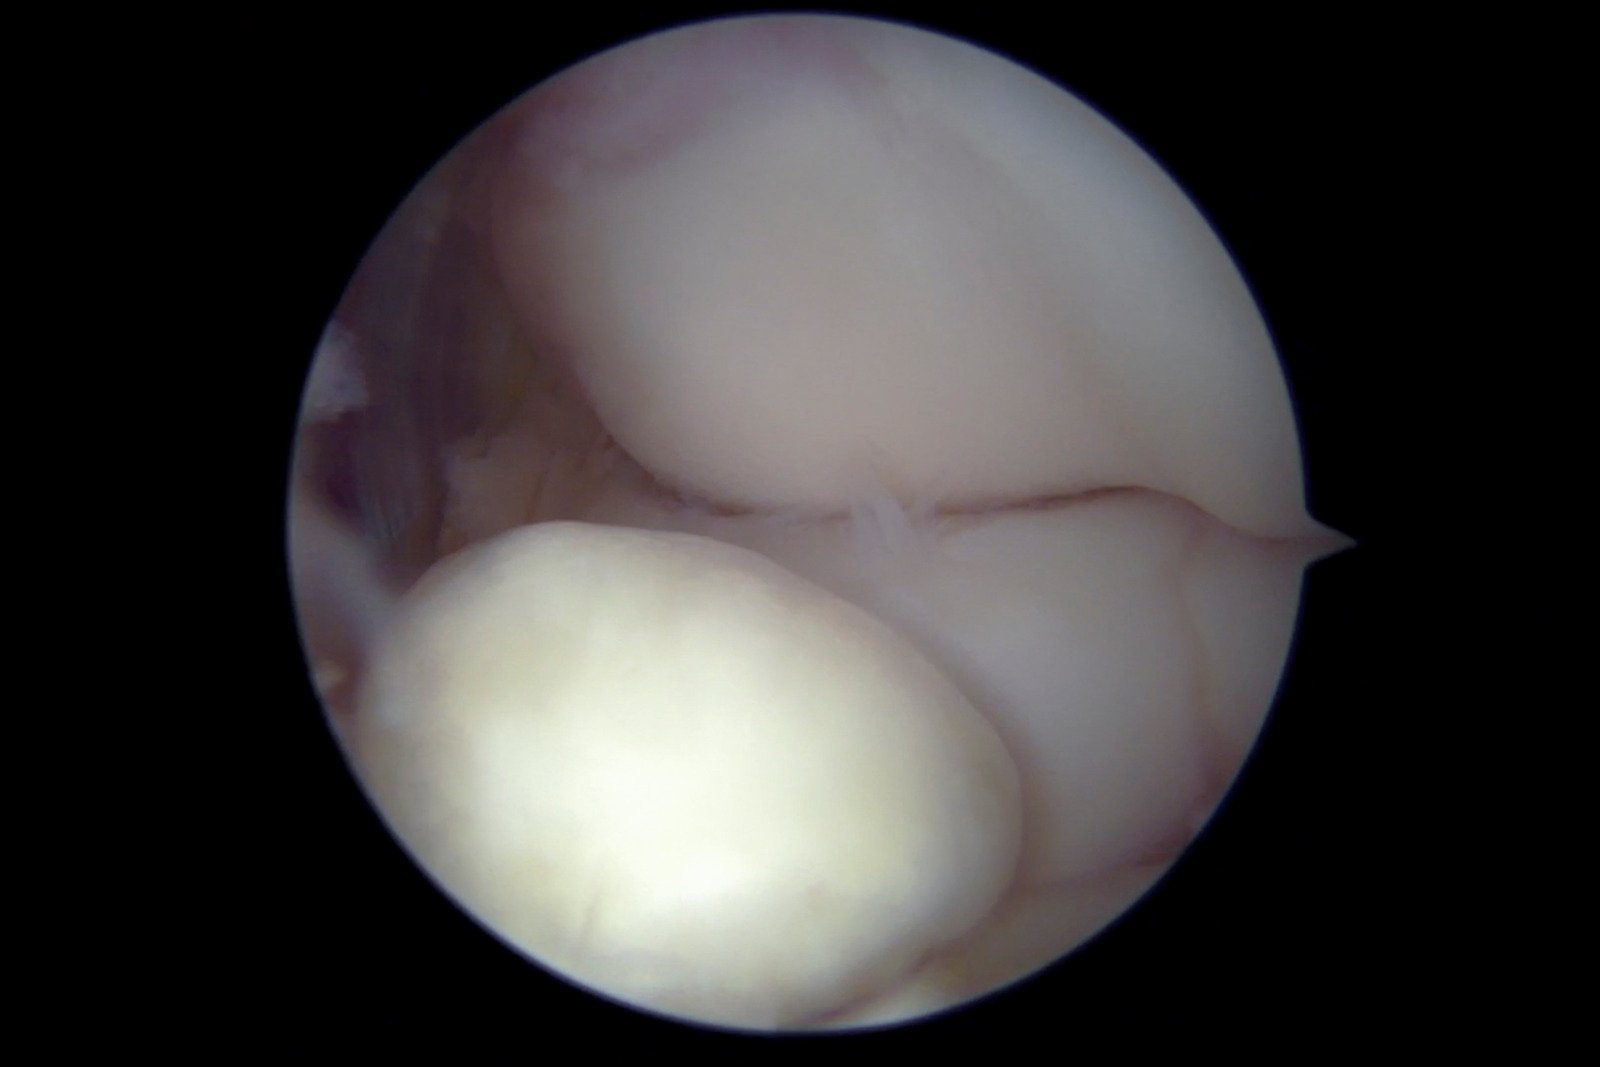

일부 경우에는 관절경 검사를 실시할 수 있습니다.

관절경 검사는 작은 카메라를 관절 내부에 삽입하여 직접적으로 유리체와 관절 상태를 관찰하는 방법입니다.

이 검사는 진단 뿐만 아니라 작은 유리체를 제거하는 데에도 사용될 수 있습니다.

관절경 수술: 소형 카메라와 수술 도구를 이용하여 최소 침습적 방법으로 유리체를 제거합니다. 관절경을 통한 수술은 회복 시간을 단축하고, 통증을 줄이며, 주변 조직의 손상을 최소화하는 장점이 있습니다.